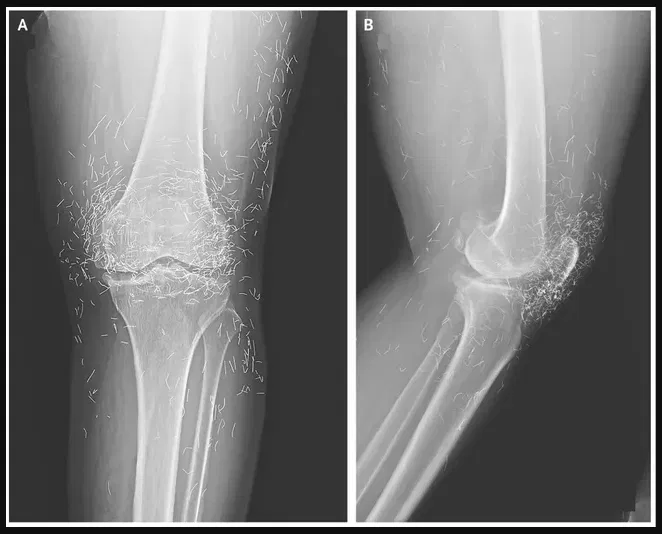

The doctors looked at an X-ray of an old woman’s knees since her joints hurt a lot. They found hundreds of small gold acupuncture needles in her tissue.

The 65-year-old woman from South Korea had already been told she had osteoarthritis, which is when the cartilage and bones in the joints break down and cause pain and stiffness. Last week, doctors wrote in the New England Journal of Medicine that she had tried acupuncture because painkillers and anti-inflammatory drugs didn’t help her knees and just made her stomach hurt.

The study further says that the needles used in the woman’s acupuncture treatment were possibly made of gold and were put in her body on purpose to make her feel better.

It might also make it such that a doctor can’t see an X-ray. Guermazi said, “The needles might cover up some of the body parts.”